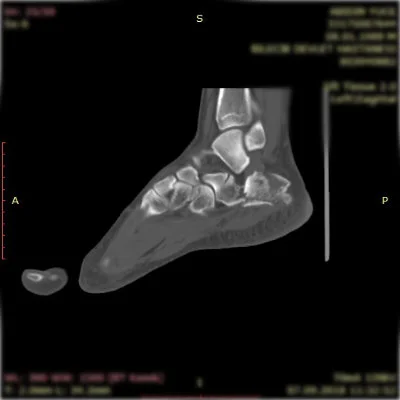

Görüntüleri büyütmek için resmin üstüne tıklayınız.